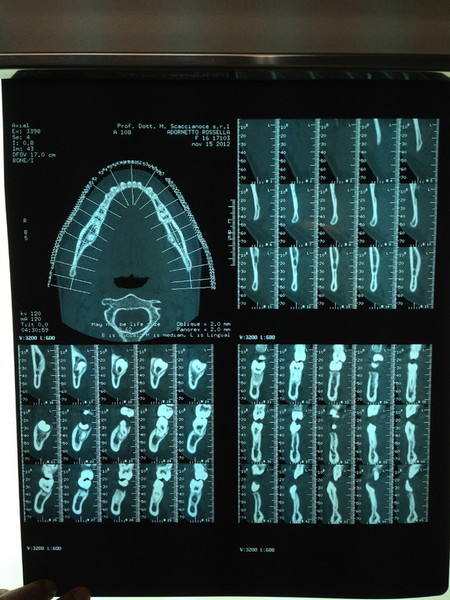

Paziente candidato a intervento di chirurgia Ortognatica